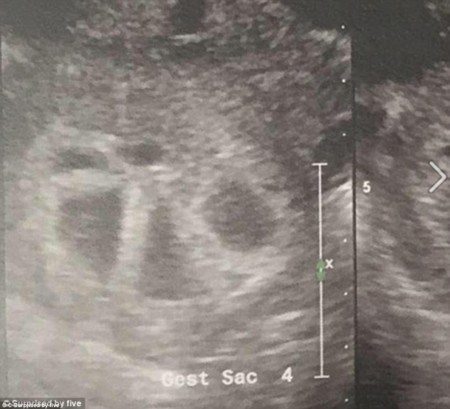

Kimberly y su pareja eran padres de dos niños cuando decidieron darle otro hermano a la parejita, la sorpresa vino cuando en una de sus revisiones del embarazo el ginecólogo le comunicó que venían cinco en camino.

Avisaron a su marido que no había podido asistir a esa revisión, pero rápidamente condujo hasta la consulta para ver con sus propios ojos a sus cinco bebés y sin parar de repetir la frase "¿pero eso es pisble?" Ha y que tener en cuenta que la probabilidad de concebir quintillizos de forma natural de de 1 entre 55.000.000(cincuienta y cinco millones) Está claro que ese día les todo el primer premio y venía con bote.